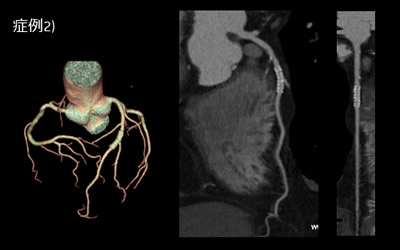

症例1) 60歳台 男性

腹部大動脈瘤に対するEVAR術前の検査

大動脈瘤術前検討の3D-CTAに加えて、冠動脈のスクリーニングを目的にCT検査を施行した。

冠動脈狭窄が認められないことが容易に判定できる。